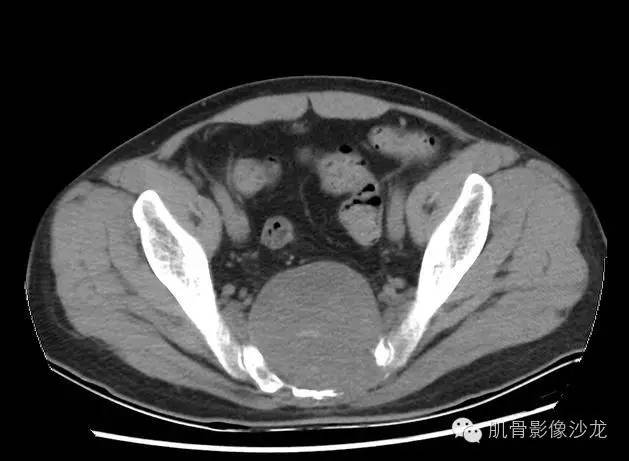

男,43岁,骶尾部疼痛、麻木8月

影像表现:骶骨中下部见溶骨性骨质破坏,破坏区见软组织肿块影,边缘无硬化,其内密度不均,可见散在钙化灶,未见骶管、骶孔扩大;强化轻,未见明显坏死。

1、发病部位,有利于脊索瘤的诊断,不利于骨巨的诊断。

2、内可见钙化,有利于脊索瘤的诊断,不利于骨巨的诊断。

3、发病年龄,不利于动脉瘤样骨囊肿的诊断。

4、强化轻,未见明确坏死,未见骶管、骶孔扩大;不利于神经源性肿瘤的诊断。